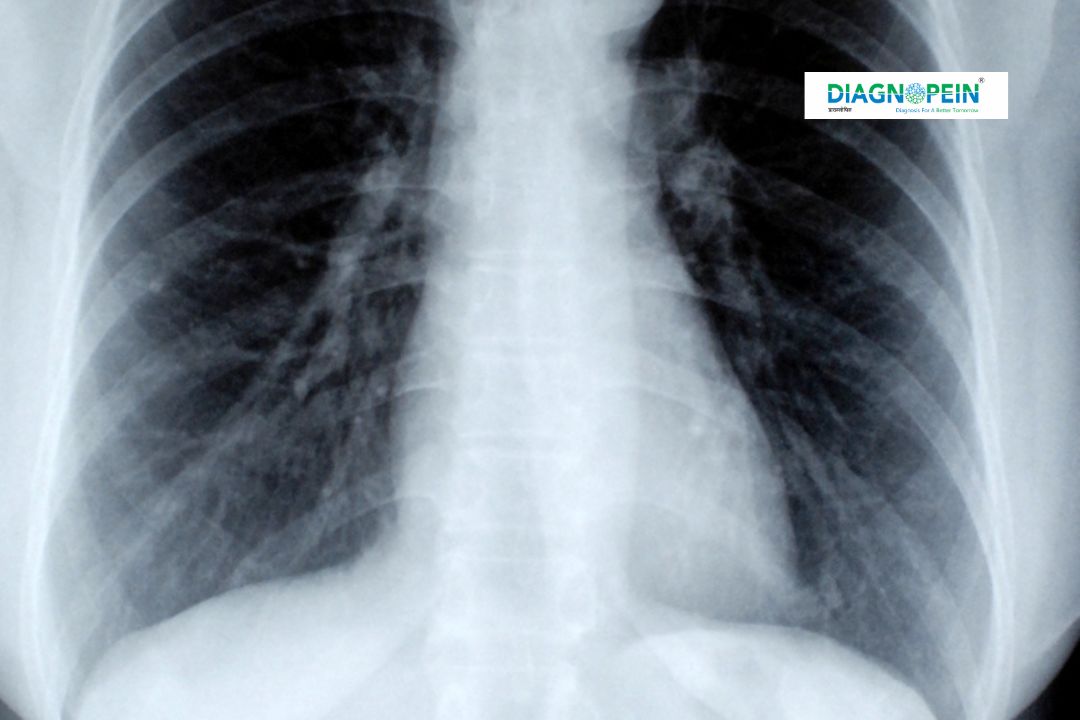

Oblique View X-Ray is a specialized imaging technique used to capture angled perspectives of bones and joints that are not clearly visible in standard front or side radiographs. This technique is crucial in detecting subtle fractures, bone deformities, or hidden joint pathologies. At SmartView Oblique Karad, patients receive precise imaging designed to reveal critical diagnostic details that enhance medical evaluation and treatment planning.

Oblique X-Ray imaging holds high diagnostic value because it provides an alternate angled projection, helping clinicians visualize overlapping structures with greater clarity. It is especially beneficial for examining the spine, chest, ribs, and peripheral joints.

Facilities such as SpineSight Oblique Karad rely on this advanced method to detect fractures, dislocations, and bone misalignments that may not appear in standard anterior or lateral X-rays. The Oblique View reduces diagnostic errors, ensures proper alignment assessment, and supports physicians in preparing treatment strategies for musculoskeletal conditions.